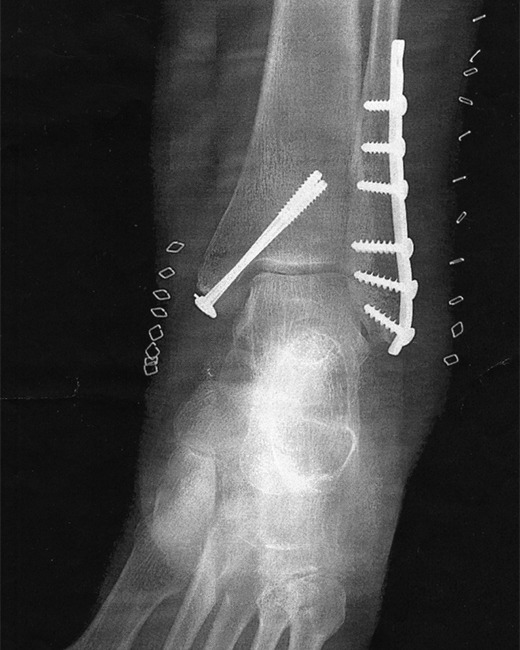

Dr. Larson’s training at The Carolinas Medical Center, in Charlotte, NC - one of the country’s premier orthopedic residency training programs - has well prepared him for traumatic injuries to the lower extremity as well. Since coming to Denton, Dr. Dr. Larson consistently treats a variety of lower extremity conditions and takes general orthopedic call at Texas Health Presbyterian Hospital in Denton, TX.

Hip fractures, which come in many different varieties, as well as long bone fractures to the femur (thigh bone) or the tibia or fibula (bones in the lower leg), and ankle fractures unfortunately are quite common. Proper treatment of these conditions requires skill, knowledge, and often a team approach to get patients the care they deserve so they can get back on their feet.